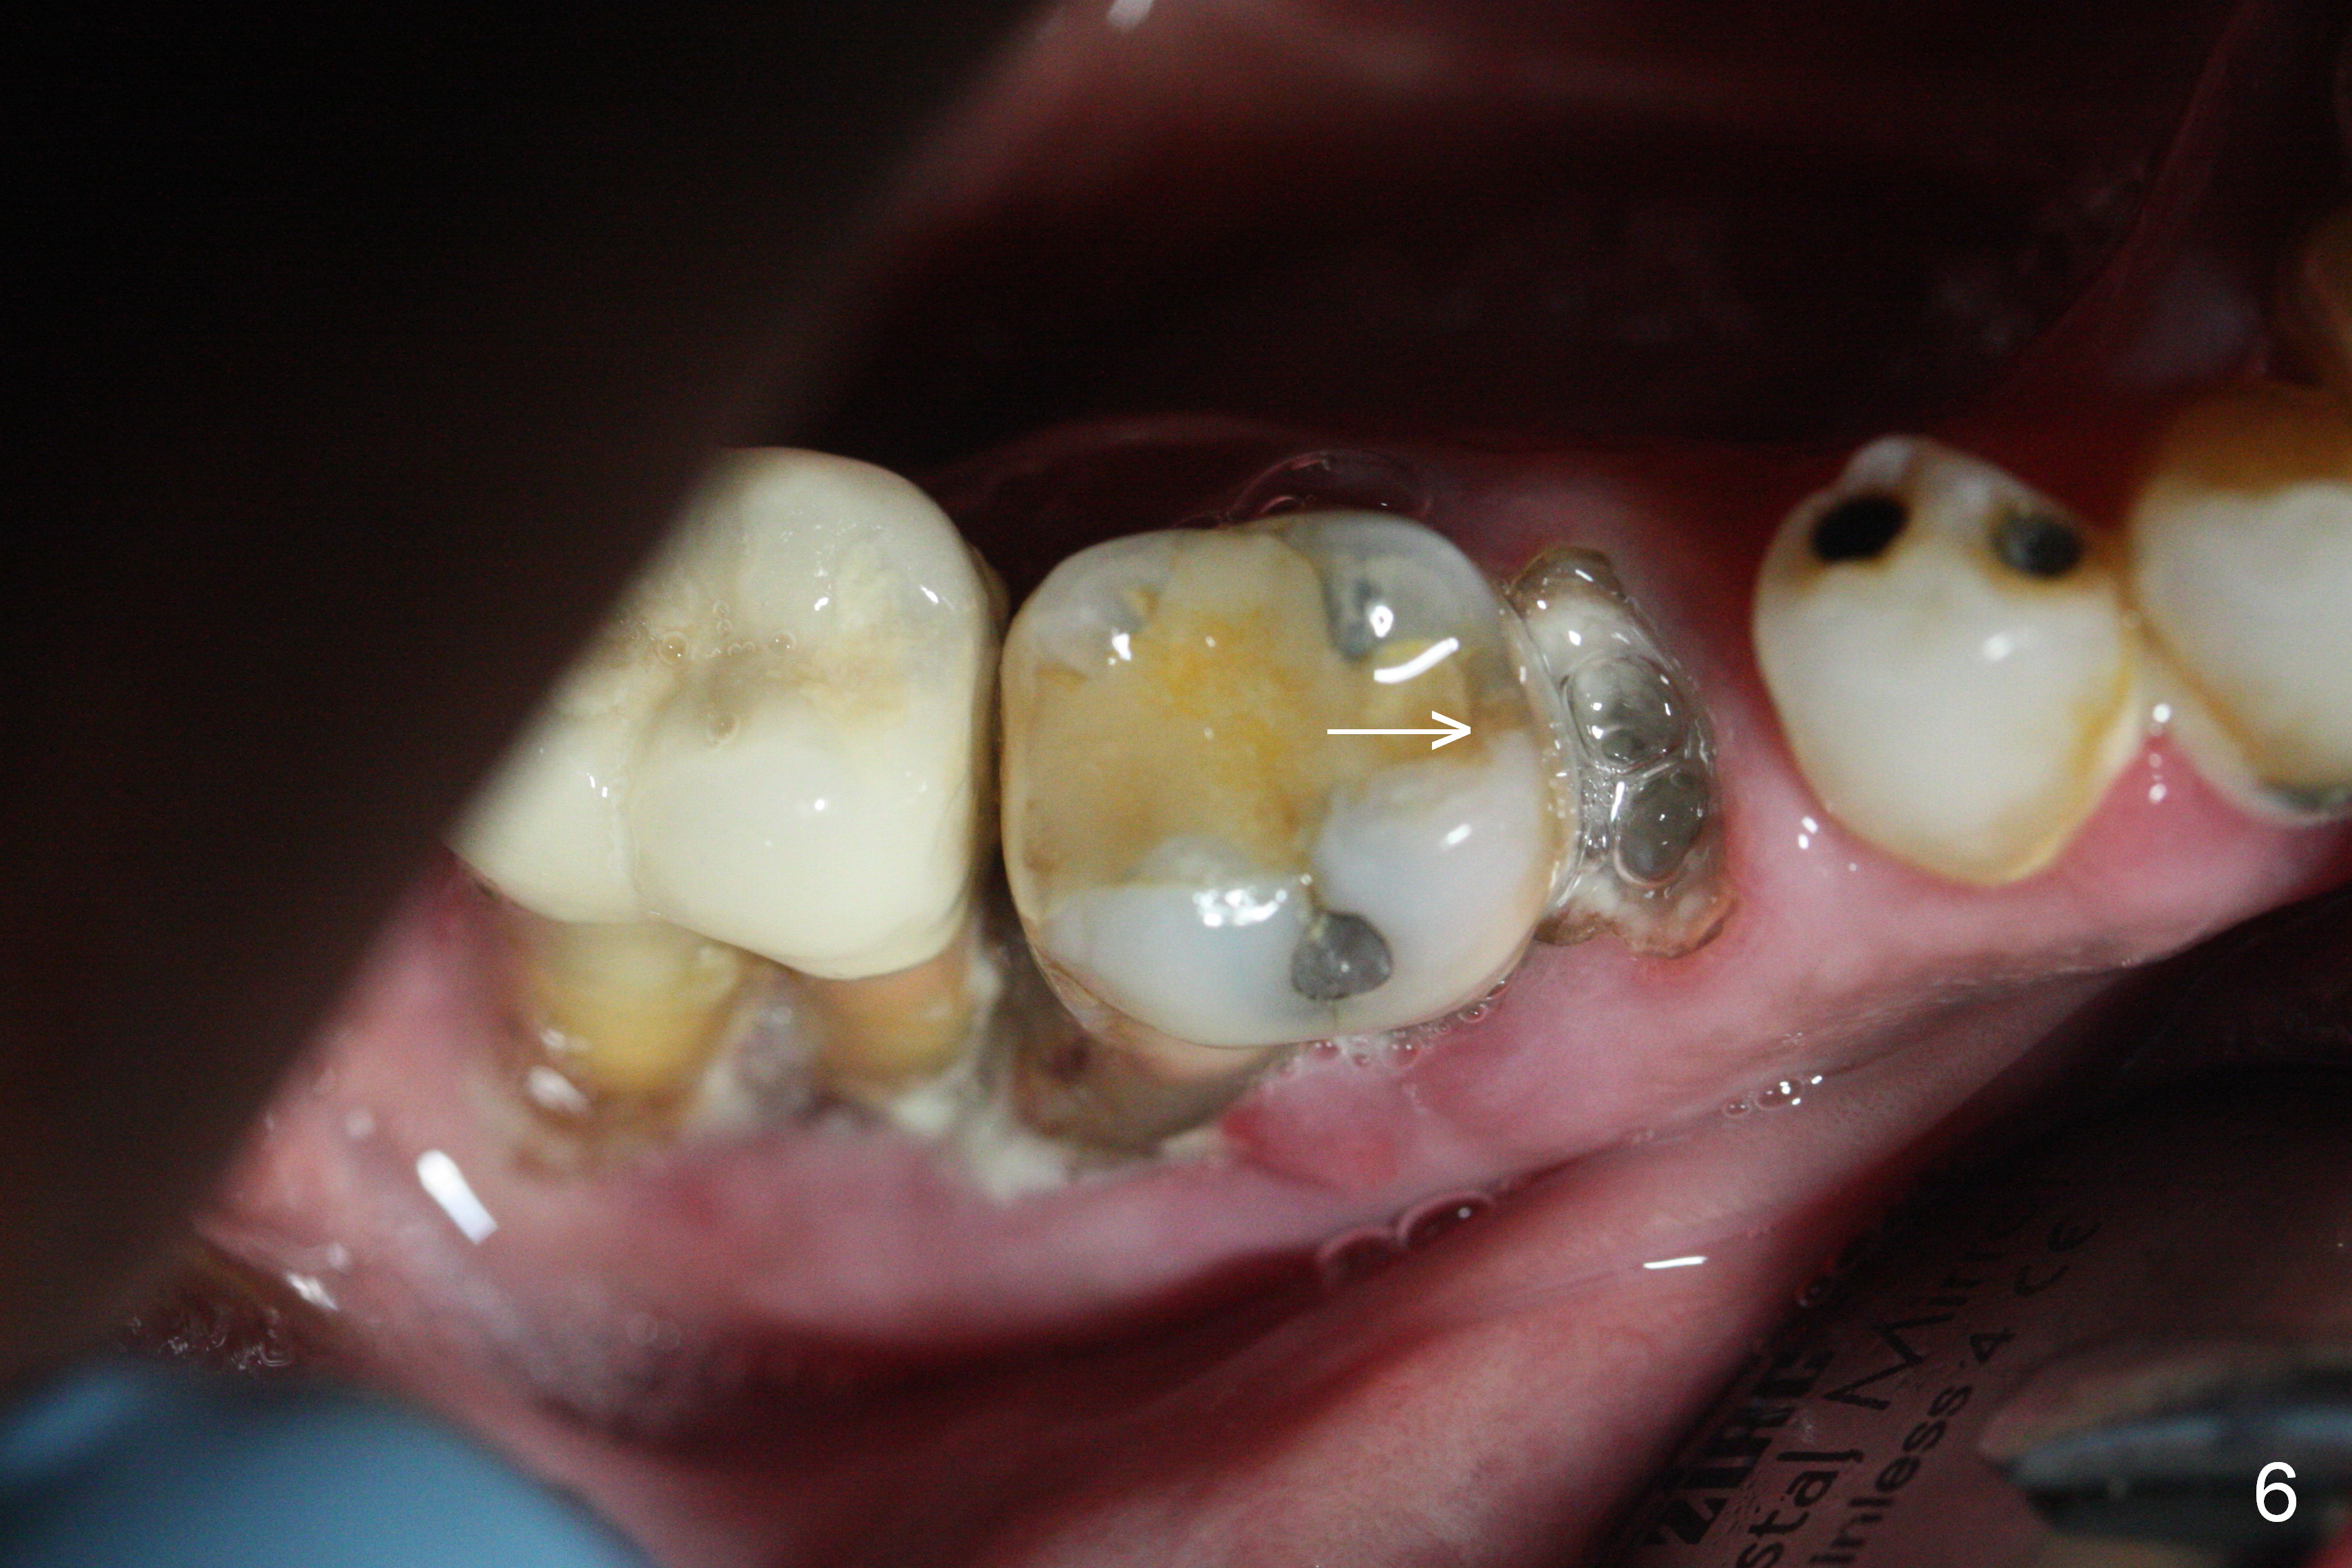

A 71-year-old man had poor dentition 4 years ago (Fig.1). Since then severe bone loss has occurred at the teeth #2 (Fig.2 *), 30 and 31 (Fig.3 *). An original plan is to place implants at #29 and 31 and fabricate a 3-unit bridge. Since the bone height at #31 is limited, primary stability may be questionable. It is advantageous to place 3 implants at #29-31. As the bone loss is severe and the sockets at #30 and 31 are long (Clindamycin), a fairly long portion of the implants at #30 and 31 will be not covered by the native bone (Fig.4 yellow line: 6-7 mm, bare) in spite of using 6 mm cuff (pink) of 7 mm abutments (brown). Use initial drill from DIO Sinus Master Kit with 5 mm stopper at #31 (green line), followed by insertion of a marked parallel pin. Use regular drills with stoppers of 10 and 8 mm at #29 and 30 (green line). Continue osteotomy at #31 with round drills (2.8 and 3.6 mm) with shorter stopper to avoid injury to the underlying Inferior Alveolar Canal (red dashed line). Pack allograft well around the implants at #30 and 31 before placing abutments to reduce periimplantitis and insert collagen plug around the abutments to prevent loss of the bone graft underneath. The last method to secure the bone graft is a retentive, splinted provisional.

It appears that the endo perio disease is more severe than 6 months ago (Fig.5,6). Prepare PRF and Extra Wide implants as well.